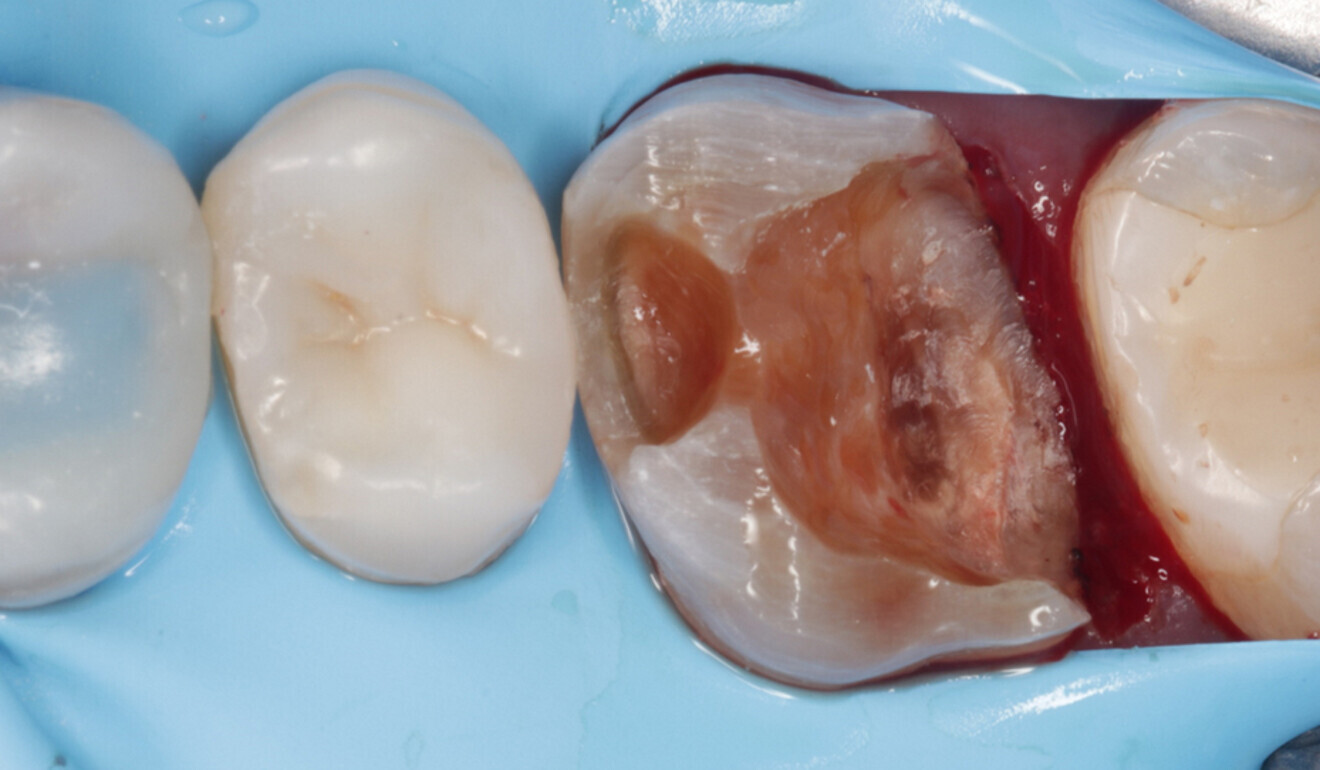

In accordance with the European Society of Endodontology’s guidelines on the management of deep caries,10 the deepest part of the cavity was cleaned under full dental dam isolation (Nic Tone, MDC Dental; Fig. 6). Carious tissue excavation was carried out using round burs and then the enamel and dentine were air abraded with 50 μm aluminium oxide (MicroEtcher IIA, Danville Materials). Multiple cracks, penetrating through the enamel and partially the dentine, had occurred within the mesial and palatal walls. The presence of cracks crossing the amelodentinal junction is an absolute indication for cuspal coverage.8, 11

Fig. 6: Dental dam newly placed in the interproximal area. Full isolation is essential for the excavation of the infected dentine in the deepest part of the cavity. (Image: Kuraray Noritake Dental)